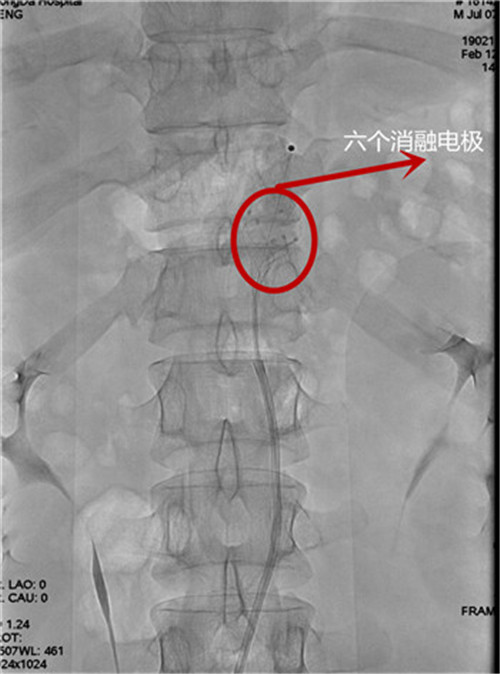

電極植入到腹主動(dòng)脈

據(jù)介紹,血管內(nèi)去交感神經(jīng)術(shù)治療糖尿病,這種介入微創(chuàng)手術(shù)在局麻狀態(tài)下進(jìn)行,細(xì)長(zhǎng)導(dǎo)絲從股動(dòng)脈進(jìn)入,在血管造影下精準(zhǔn)定位,運(yùn)用帶六位電極的螺旋環(huán)通過(guò)射頻消融,毀損腹腔動(dòng)脈周?chē)慕桓猩窠?jīng),讓活躍的交感神經(jīng)進(jìn)入“休眠期”,從而起到降低血糖的效果。根據(jù)目前的研究,糖尿病患病史少于10年、年齡在18到75歲之間罹患頑固型2型糖尿病、合并代謝綜合征、多種藥物控制不佳的糖尿病患者,可以嘗試這種介入微創(chuàng)方法治療。